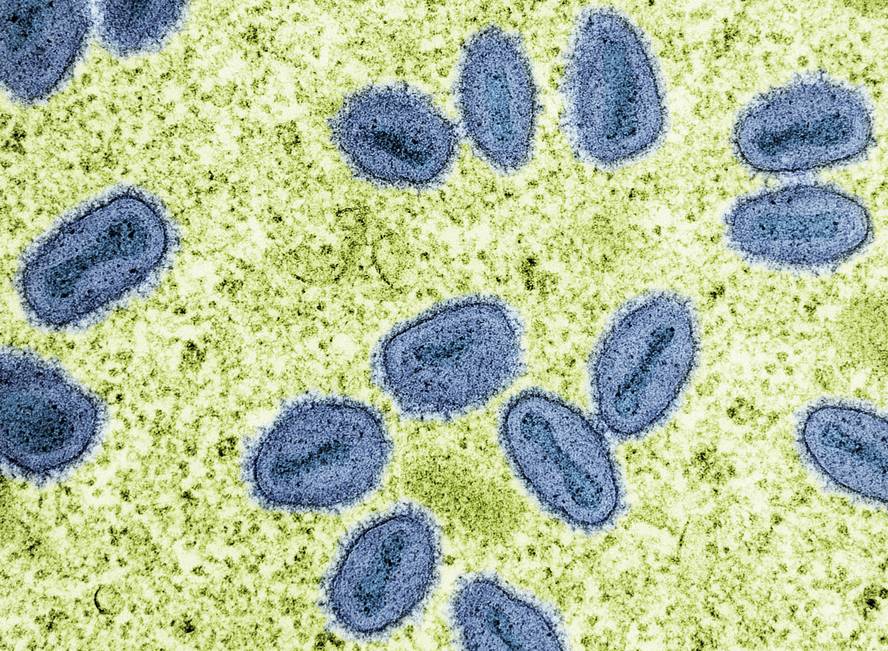

En la llista renovada, s'han considerat prop de 30 els preferents, entre els quals es troben virus com els Sarbecovirus (un d'ells és el SARS-CoV-2), T-baztanga, grip A (incloent el subtipus H5), ébola, zika... i bacteris com el còlera, la disenteria, la pneumònia...